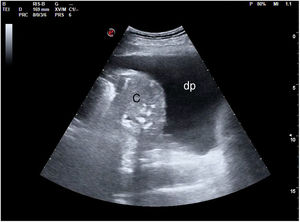

La pérdida total de aireación dará un patrón de consolidación, como sucede por ejemplo en la neumonía o la atelectasia (fig. 18). En el síndrome alveolar, en que el aire ha sido sustituido por inflamación o tejido consolidado, la ecografía obtendrá una imagen anatómica del pulmón. El órgano se mostrará con una apariencia tissue-like, de ecogenicidad similar a la del hígado, pudiendo presentar broncograma aéreo (hiperecogénico) o fluido (anecogénico), y su vascularización podrá ser estudiada mediante doppler color. Algunas consolidaciones pueden presentarse con derrame pleural asociado (fig. 19).

Derrame pleuralSe visualizará como la presencia de líquido entre la pleura parietal y la visceral; anecogénico en los trasudados, pudiendo tener cualquier aspecto en los exudados (desde anecogénico hasta derrames pleurales complejos, tabicados y con contenido ecogénico)46. Se puede estimar la cantidad de derrame47, así como anticipar la complejidad de la toracocentesis (permite prever la necesidad de agujas de mayor calibre en derrames complejos, la dificultad de drenaje en los tabicados o determinar el mejor abordaje). El uso de la ecografía durante la toracocentesis permite guiar la aguja, mejorando la precisión y minimizando el riesgo de complicaciones, por lo que es altamente recomendable48.